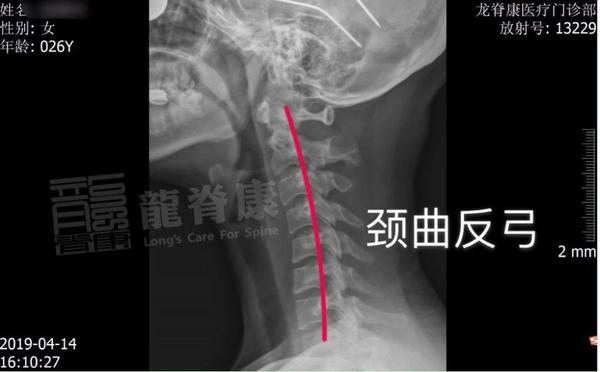

颈椎生理曲度变直目测方法及康复易忽视环节

颈椎生理曲度变直消失怎么回事